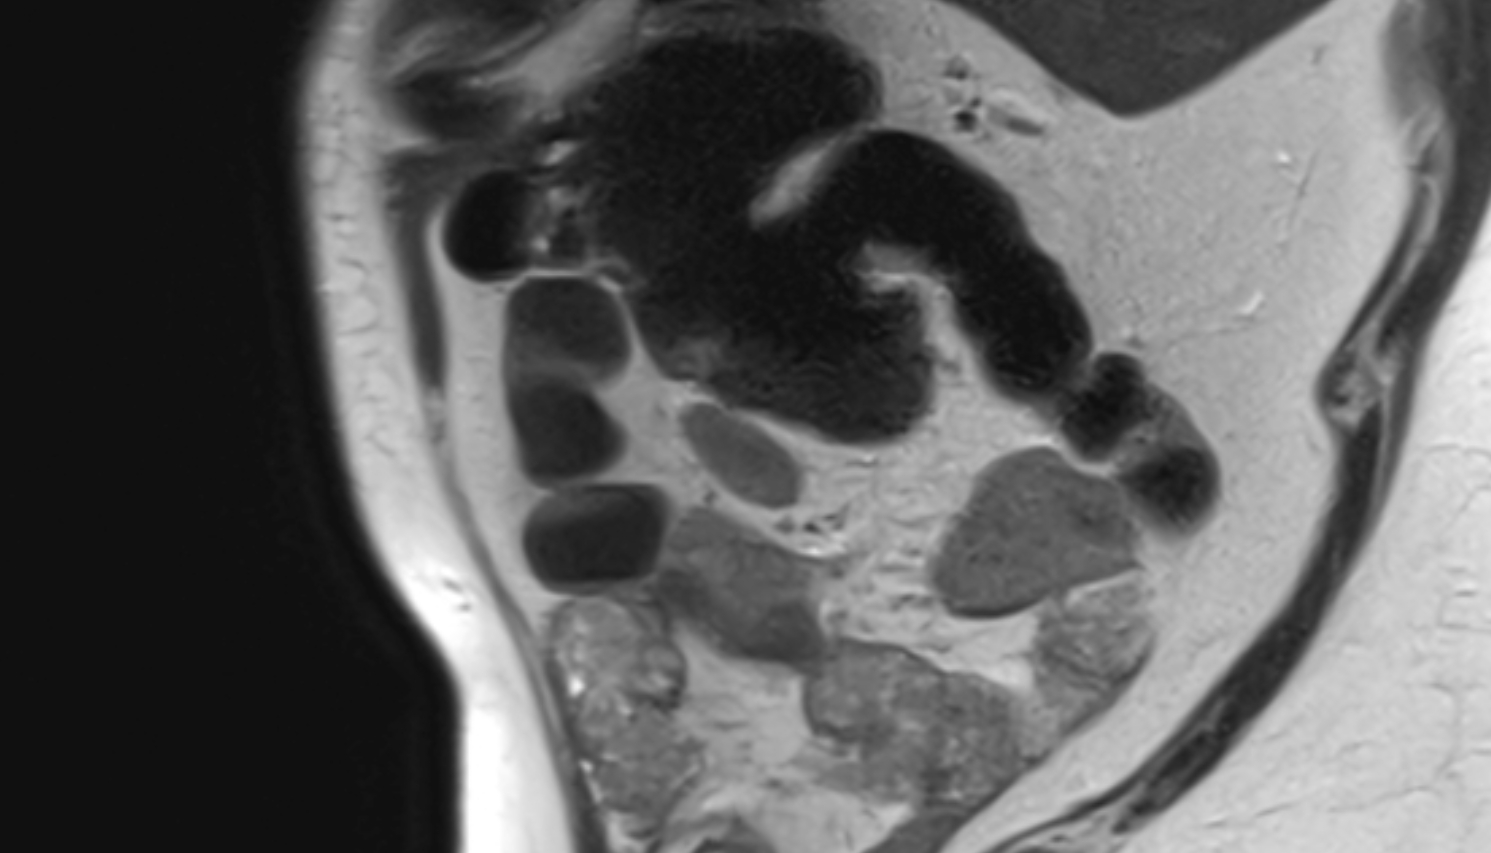

- Placenta

- Uterus (pregnancy)

- Amniotic fluid

- Umbilical cord

- Urinary Bladder in Pregnancy

- Cervix in Pregnancy

- Vagina in Pregnancy

- Fundus of uterus in pregnancy